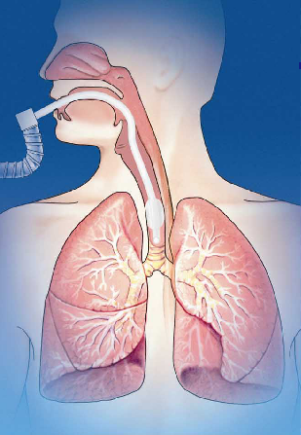

胎粪进入支气管和肺内

asphyxia, meconium aspiration

1.气管插管,尽量吸净suction